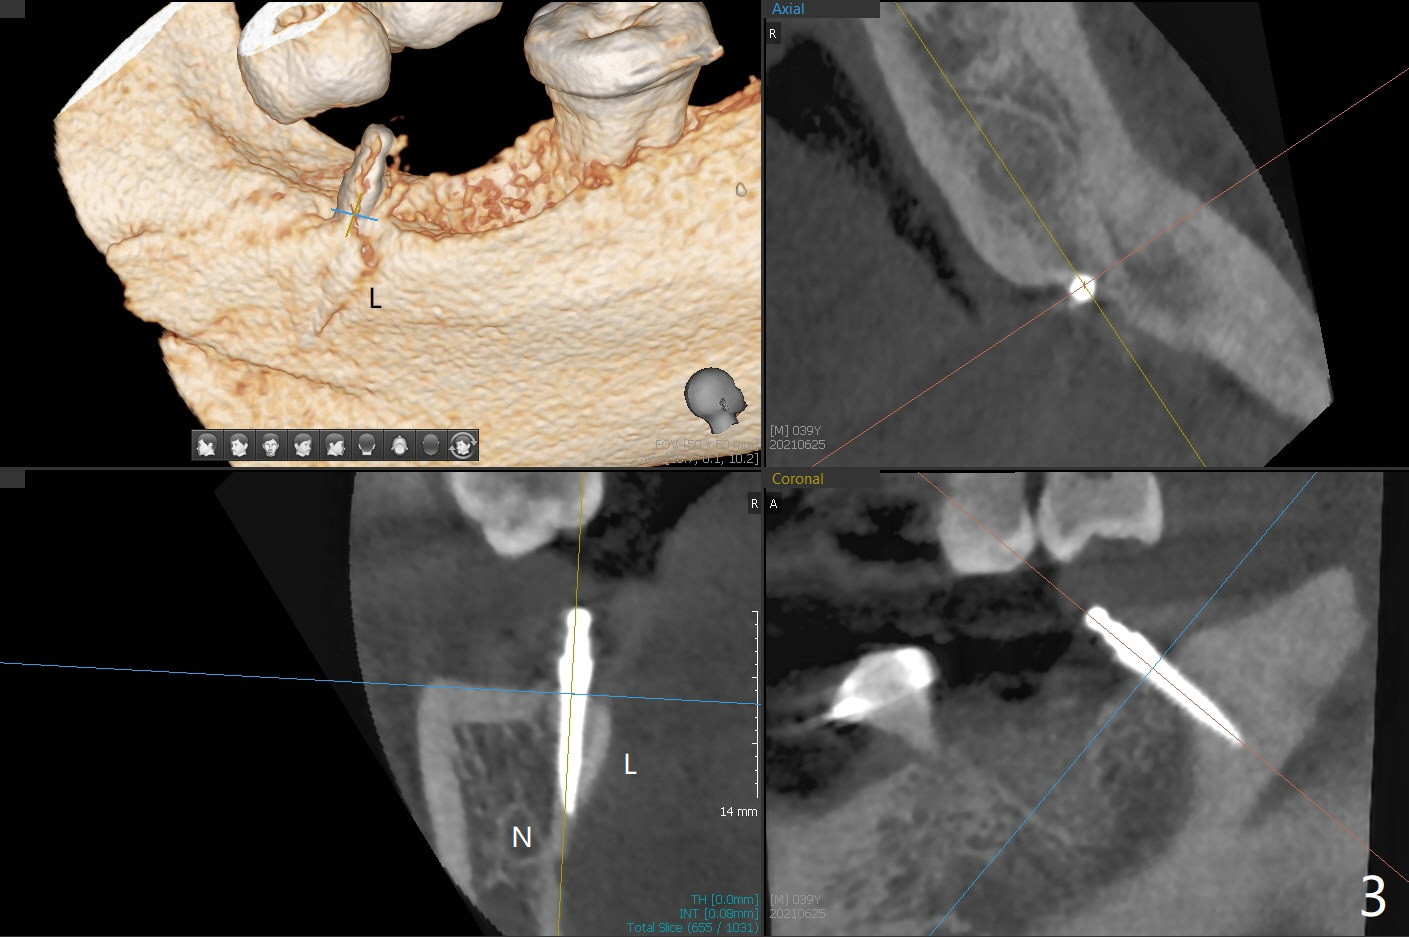

#17牙拔除植骨后1.5月(图一),准备在牙槽窝远中,即升支,种植一个抛锚,局麻下,首先不切开,钻洞,有些不放心,后来切开植入2x10(2)毫米一段式带球状基台植体(图二),植体根尖好像进入神经管(N)。CT显示植体却植入太接近舌侧骨板(图三:L),其实应该术前拍摄CT。由于18号牙同时扭转,安置磨牙圈(molar band),利用power chain进行牵拉以及矫正扭转(图四)。问题:升支抛锚种植位置对吗?power chain挂在抛锚上不稳定。